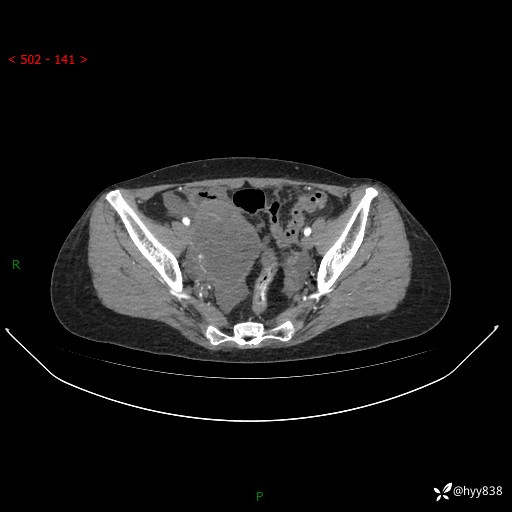

老年女性,尿频2月。超声发现盆腔囊实性占位,CT能否明确诊断---结果公布

现病史:患者绝经3-4年,期间无阴道出血及排液。患者近2月感尿频,自行口服中药治疗,症状无明显缓解。2024-4-25日于我院门诊就诊,行阴道彩超示:子宫肌瘤(大小约12*10mm,后壁),子宫右前方囊实性占位性病变(大小约126*82mm肿块声像,边界尚清,以无回声为主,可见范围约84*27mm稍高回声),内膜3mm。建议手术治疗。门诊以“卵巢囊肿”收入院。 病程中精神、食欲、睡眠可,大小便正常,体重体力无明显变化。

腹盆CT平扫

增强